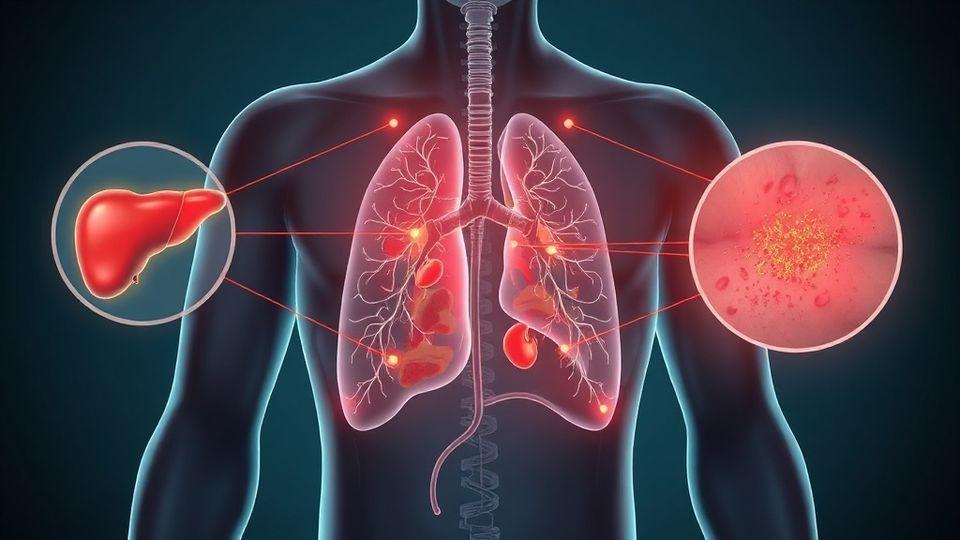

🔍 간, 신장, 폐의 가려움증 경고 신호

손바닥과 발바닥이 속에서부터 뜨겁게 가렵고 밤에 심해진다면 간과 담도 문제를 의심해보셔야 합니다. 양쪽 정강이와 발목이 대칭적으로 가렵고 소변에 거품이 생긴다면 신장 건강을 점검해야 합니다. 등 상부가 활동할 때 더 심하게 가려운 경우에는 폐의 신경이 자극받고 있을 가능성이 있습니다. 📈